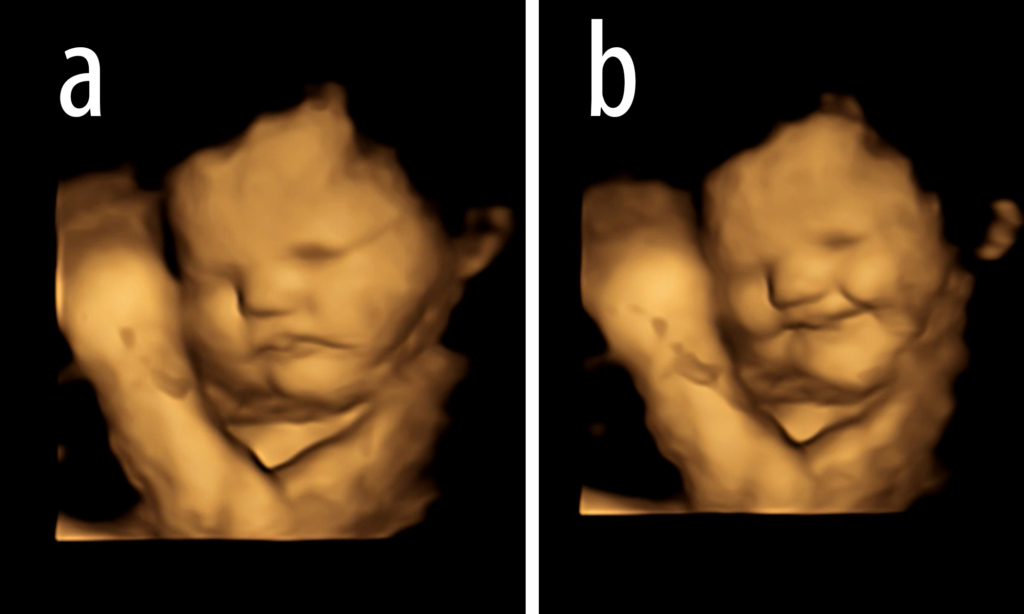

Các nhà nghiên cứu đã sử dụng phương pháp siêu âm 4D mã hóa và xác định được những chuyển động phức tạp trên khuôn mặt của em bé khi mẹ ăn cà rốt (có vị ngọt) và cải xoăn (có vị đắng) và xác nhận giả thuyết của họ là đúng: những em bé có mẹ ăn cà rốt có nhiều nụ cười hơn, những bé có mẹ ăn cải xoăn có nhiều biểu hiện khóc trên khuôn mặt hơn. Các chuyển động trên khuôn mặt của bé được đo theo từng khung hình, tiết lộ phản ứng khi mẹ bé ăn các loại thức ăn khác nhau.

Các nhà nghiên cứu phát hiện ra rằng những thai nhi tiếp xúc với hương vị cà rốt có biểu hiện “kéo khóe môi” và “cử chỉ mặt cười” thường xuyên hơn so với những thai nhi tiếp xúc với hương vị cải xoăn – có biểu hiện “hạ môi dưới” và “cử chỉ mặt khóc.” Hương vị cà rốt tổng hợp được người lớn mô tả là “ngọt ngào” vì hàm lượng đường của nó và đôi khi cà rốt cũng có hương vị trái cây hoặc hương gỗ. Cải xoăn cũng được chọn để thử nghiệm vì có nhiều vị đắng hơn các loại rau xanh khác như rau bina, bông cải xanh hoặc măng tây.